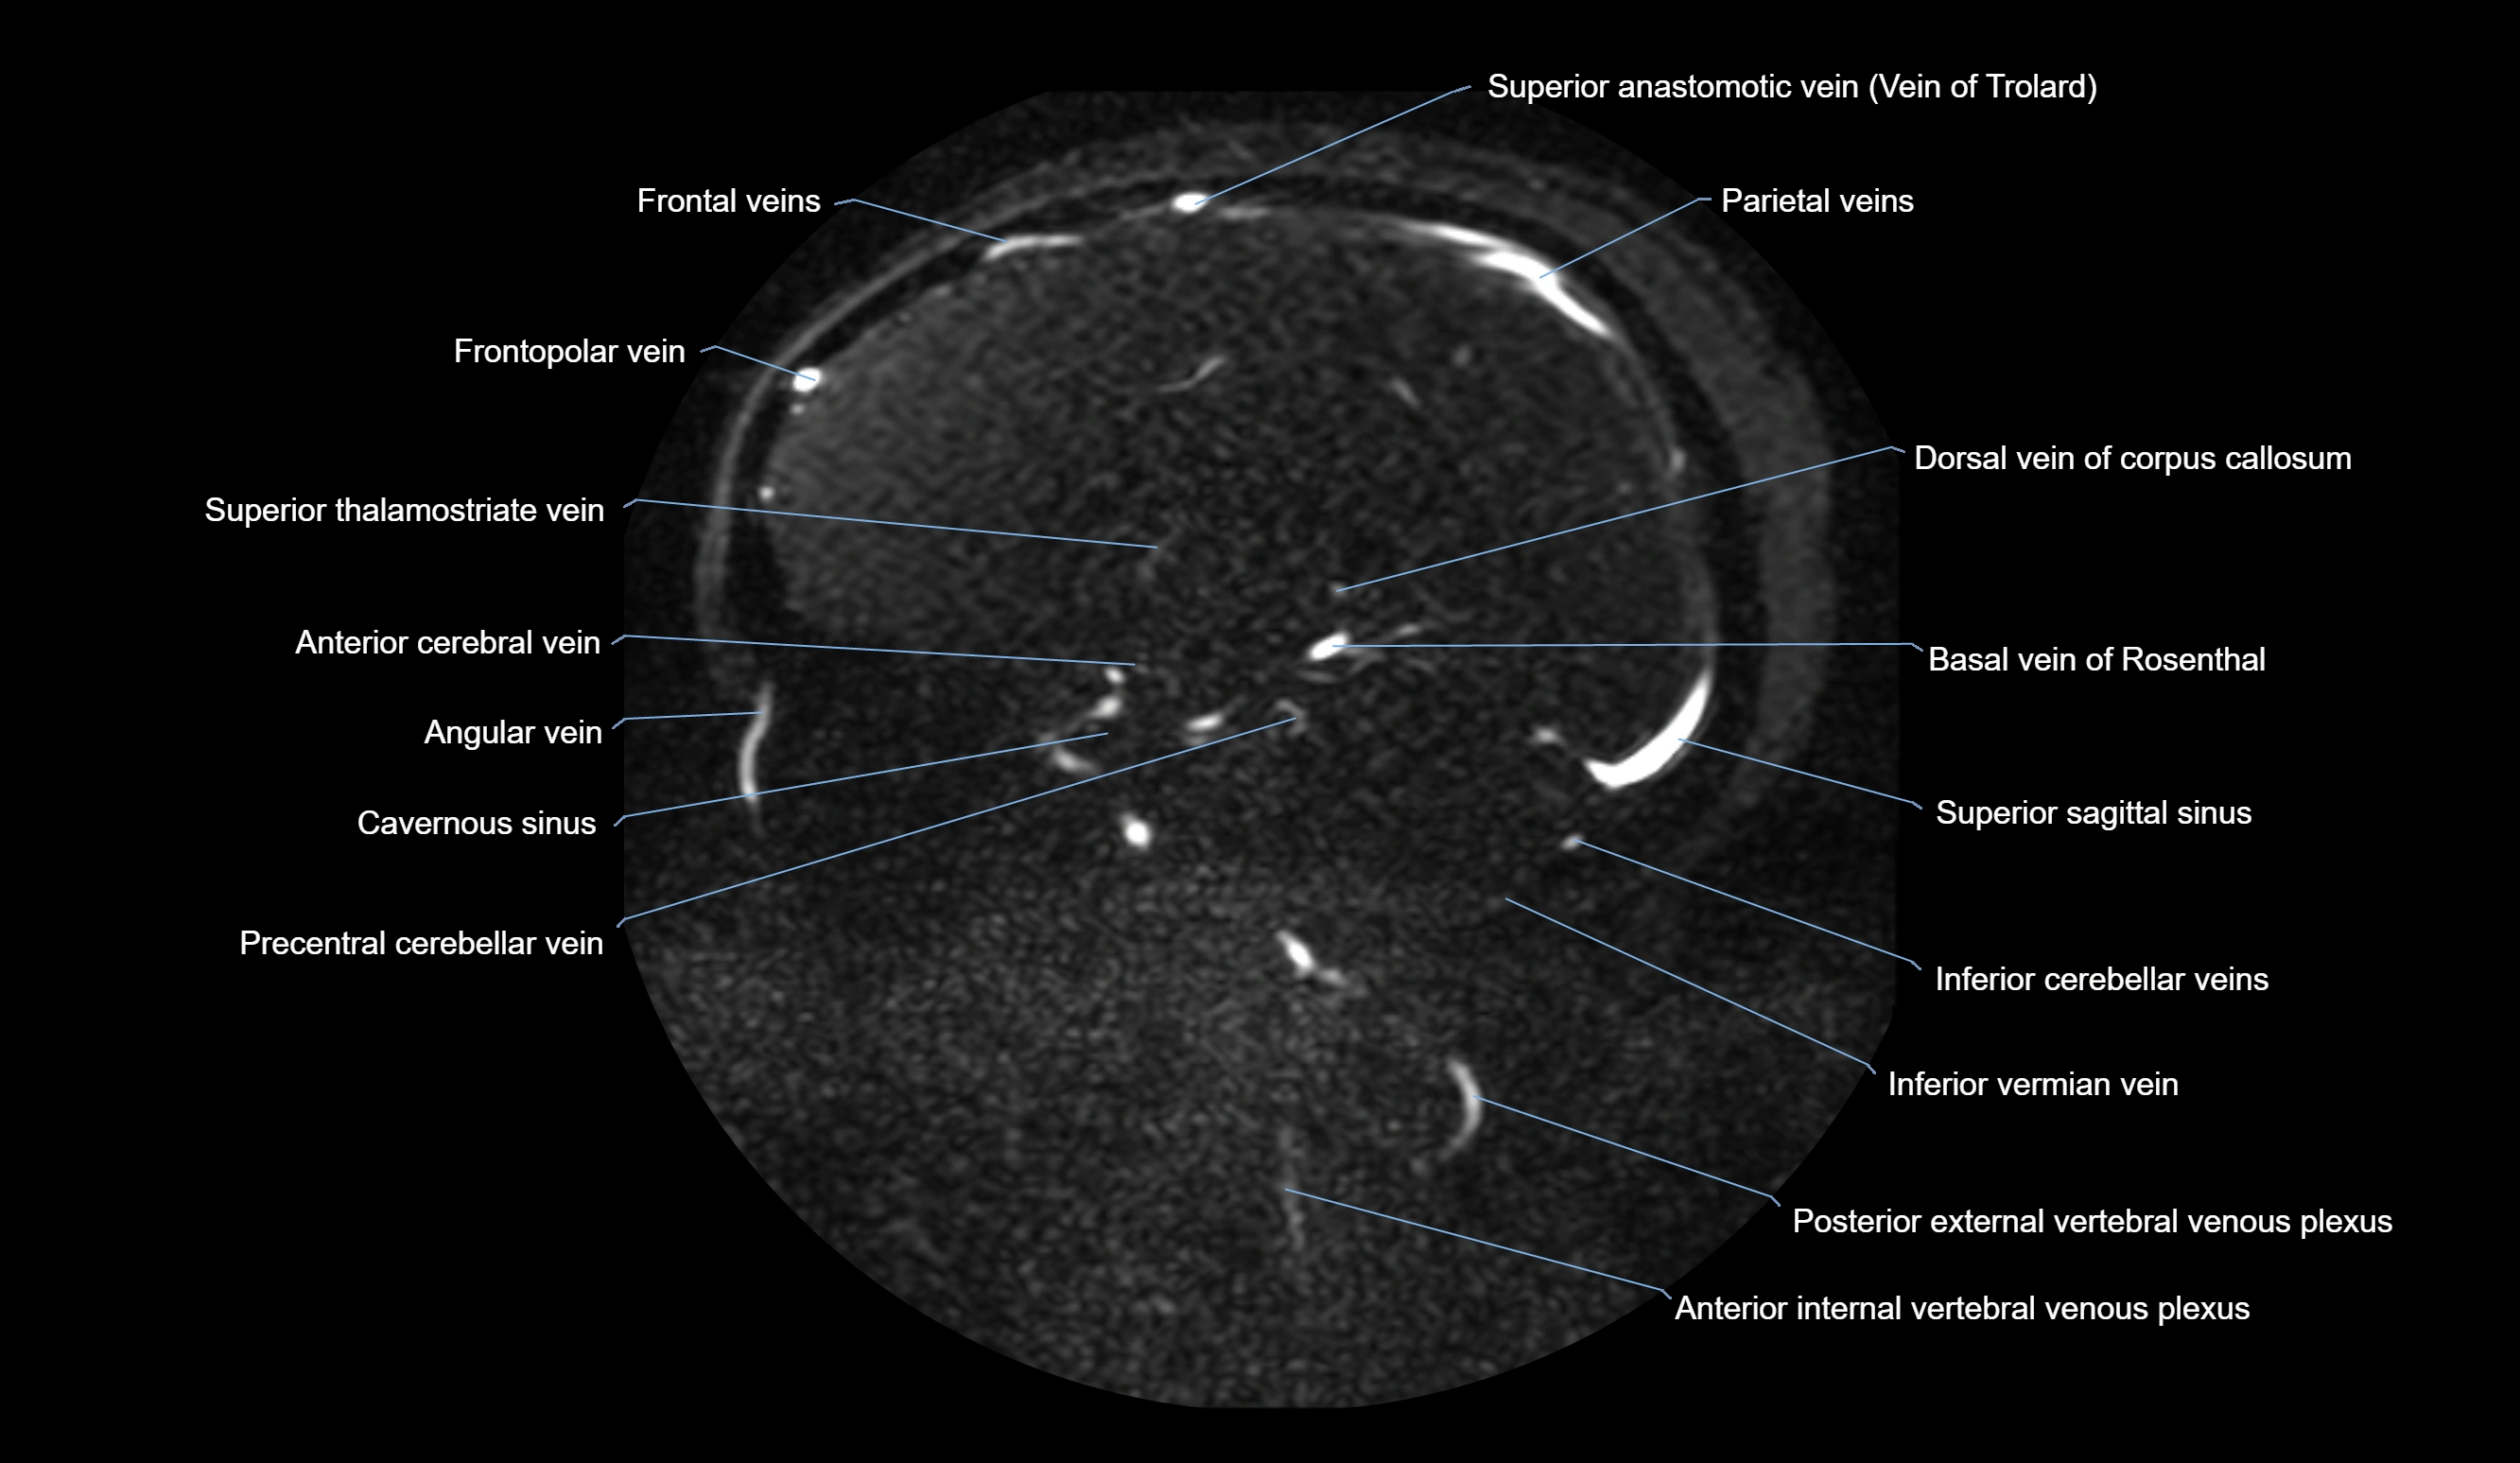

CT Venography (CTV):

• Clearly visualizes the angular vein as a contrast-filled venous channel

• Demonstrates its communication with the facial vein, superior ophthalmic vein, and cavernous sinus

• Essential for detecting facial vein thrombosis, orbital venous involvement, and cavernous sinus pathology